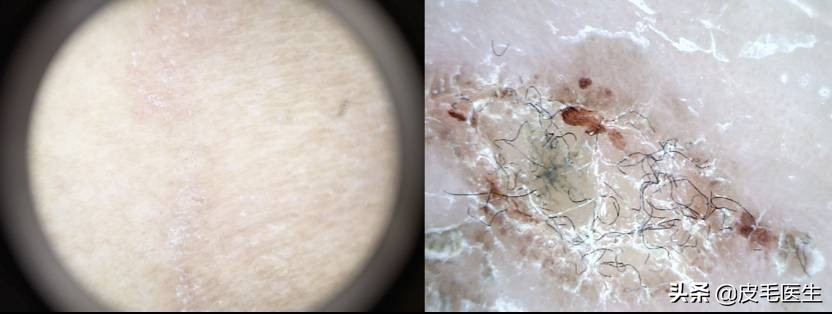

【猫狗癣】

猫狗癣是一种真菌感染,由皮肤癣菌侵害狗或猫的皮肤、被毛和趾爪角质蛋白组织等引发的各种皮肤病。癣菌常常通过猫猫狗狗“卿卿我我”的时候直接接触传染,但也可能通过美容用的器具、梳子、剪刀等间接传染。而这些皮肤癣菌到狗狗身上就是狗癣,到喵身上就是猫癣,而传到人类身上就会发生头癣(脱发)、体癣、股癣、香港脚......

据统计已发现有5种真菌能引起猫犬的皮肤病,它们是:犬小孢子菌、石膏样小孢子菌、须癣毛癣菌、奥杜安氏小孢子菌、变形小孢子菌。其中以犬小孢子菌最为多见,其次是石膏样小孢子菌,再次是须毛癣菌和奥杜安氏小孢子菌。